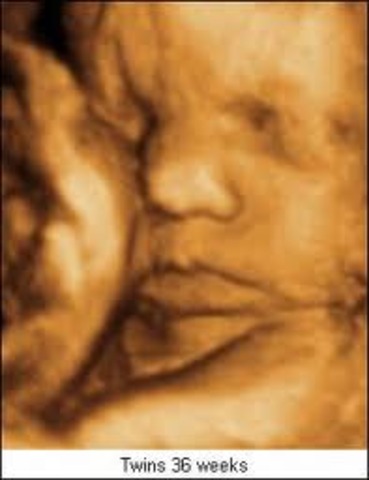

• Week 36

Week 36

Your baby is still packing on the pounds — at the rate of about an ounce a day. He now weighs almost 6 pounds and is more than 18 1/2 inches long.